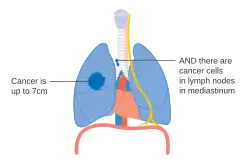

De stadiëring van niet-kleincellige longkanker (NSCLC) vindt in eerste instantie plaats aan de hand van de TNM-classificatie 8ste editie. Deze is gebaseerd op de grootte van de primaire tumor, verspreiding naar lymfeknopen (nodes) en metastasen (uitzaaiingen). Vervolgens wordt op basis van de TNM-parameters de kanker in een groep ingedeeld, die kan variëren van "occulte kanker" (kanker waar de primaire tumor nog niet gevonden is) tot de stadia 0, IA, IB, IIA, IIB, IIIA, IIIB en IV. Deze indeling in een stadiumgroep helpt bij de keuze van behandeling en het inschatten van de prognose.[43] Kleincellig longkanker (SCLC) wordt vanouds geclassificeerd als 'beperkt stadium' (beperkt tot één helft van de borst en binnen het bereik van één enkel verdraagbaar radiotherapieveld) of 'uitgebreide stadium' (verspreide ziekte).[2] De TNM-classificatie en -groepsindeling zijn echter nuttig bij het inschatten van de prognose.[43]

- Schema van belangrijkste kenmerken van longkanker stadiëring

Stadium IA en IB longkanker -

Stadium IIA longkanker -

Stadium IIIA longkanker -

Stadium IIIA longkanker, bij een of meer kenmerken zoals beschreven in de afbeelding -